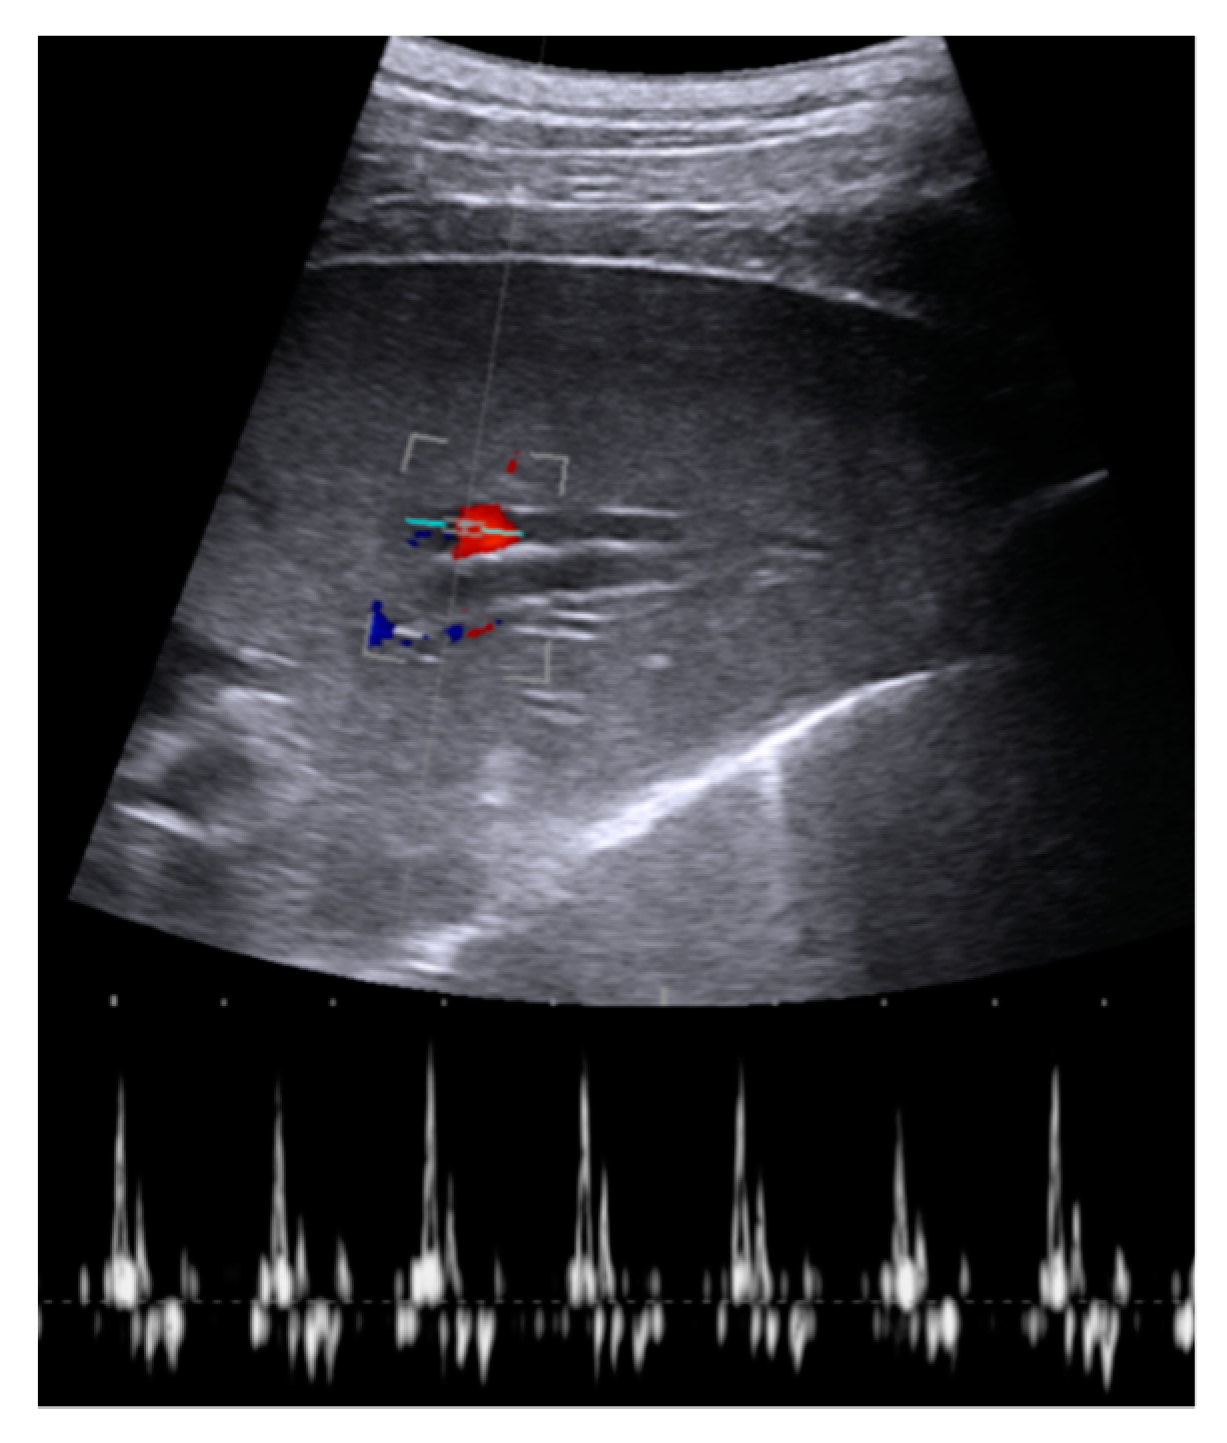

During stable flooding in-vivo with saline, unimpaired imaging without remaining air was achieved. The lung parenchyma appears homogeneous with enhanced echogenicity, where vessels and bronchi are well demarked as hypoechoic structures [18]. Trans-pulmonary imaging visualized adjacent organs such as the liver or heart (Figure 4). Doppler imaging in flooded lung is feasible and useful to detect vessels (Figure 5). No limitations regarding penetration depth were documented. High frequency linear probes (10–15 MHz) were recommended for high resolution imaging such as for small bronchi or vessels [22] (Figure 6). Using ex-vivo models and simulated intra-pulmonary nodules in-vivo, a reliable nodule detection of primary lung cancer as well as metastases were found. The tumor mass appears hypoechoic, surrounded by hyperechoic flooded lung, resulting in a high detection rate of about 100% of malignant pulmonary nodules (Figure 7), as well as simulated nodules [31]. Interestingly, the visualization is aggravated only for the bronchoalveolar cell carcinoma. The specific growth along the alveolar surface caused an echo-enhanced appearance with similar characteristics to flooded lung parenchyma [18].

Figure 5. Doppler imaging of central through flooded lung. Pulmonary artery show typical flow characteristics and adjacent bronchus with absence of Doppler signal.